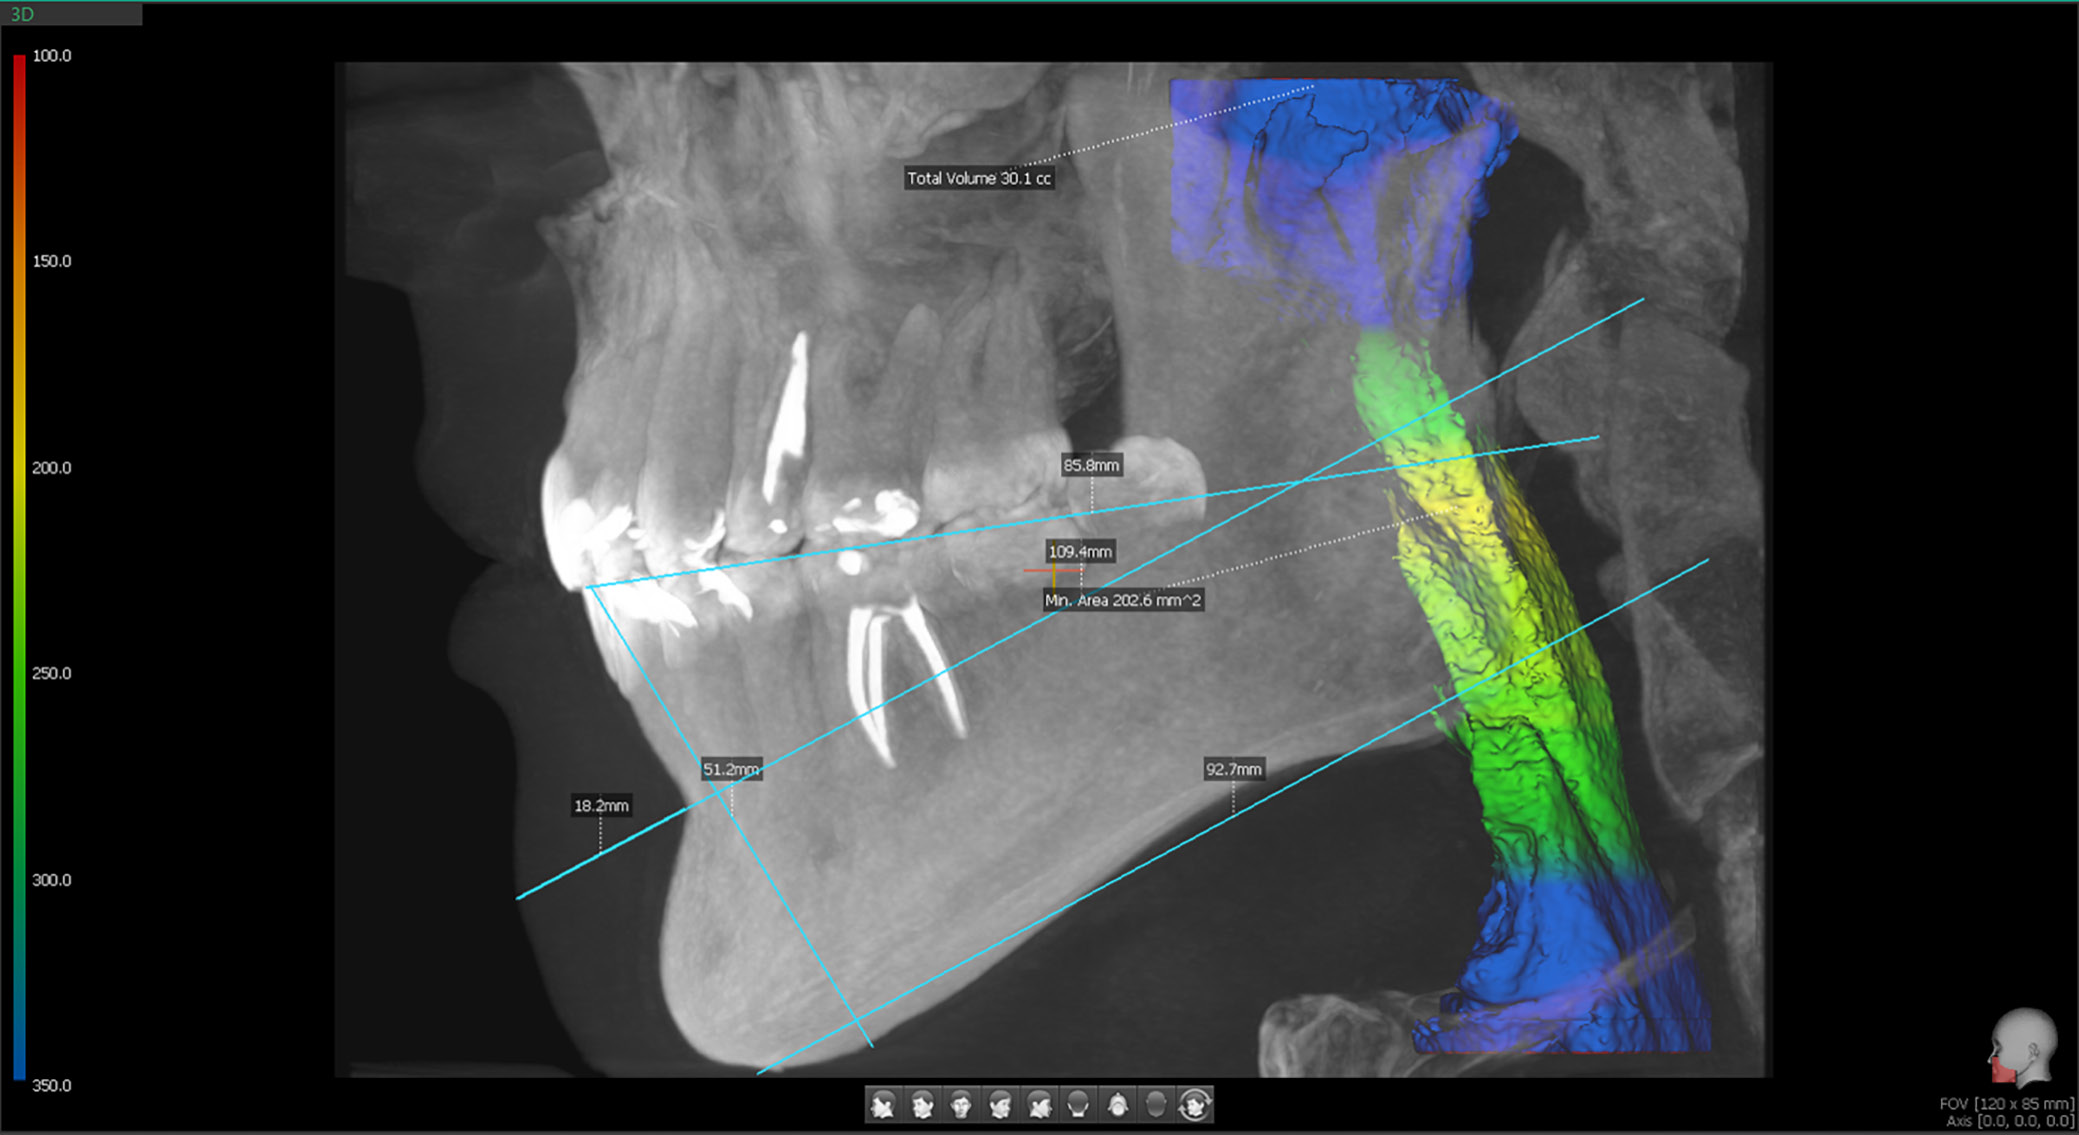

Volume of the airways

Airway measurement has become accessible to dentists through the increased use of CBCT. Thanks to built-in software, airway assessment is now one of the options available during routine X-ray examinations. It is reported – and as shown in Figure 5 below – that an airway capacity of approx. 200 mm² is considered satisfactory. To measure the airways, a CBCT scan with the full available field of view (80 mm in width and 50 mm in height) is required. Subsequently, the visible airway, extending from the nasopharynx to the sphincter, should be marked. It is known that airway narrowing is quite common in cases of malocclusion, especially in Class II malocclusion, where the retruded mandible reduces the space available for the tongue and decreases airway capacity.